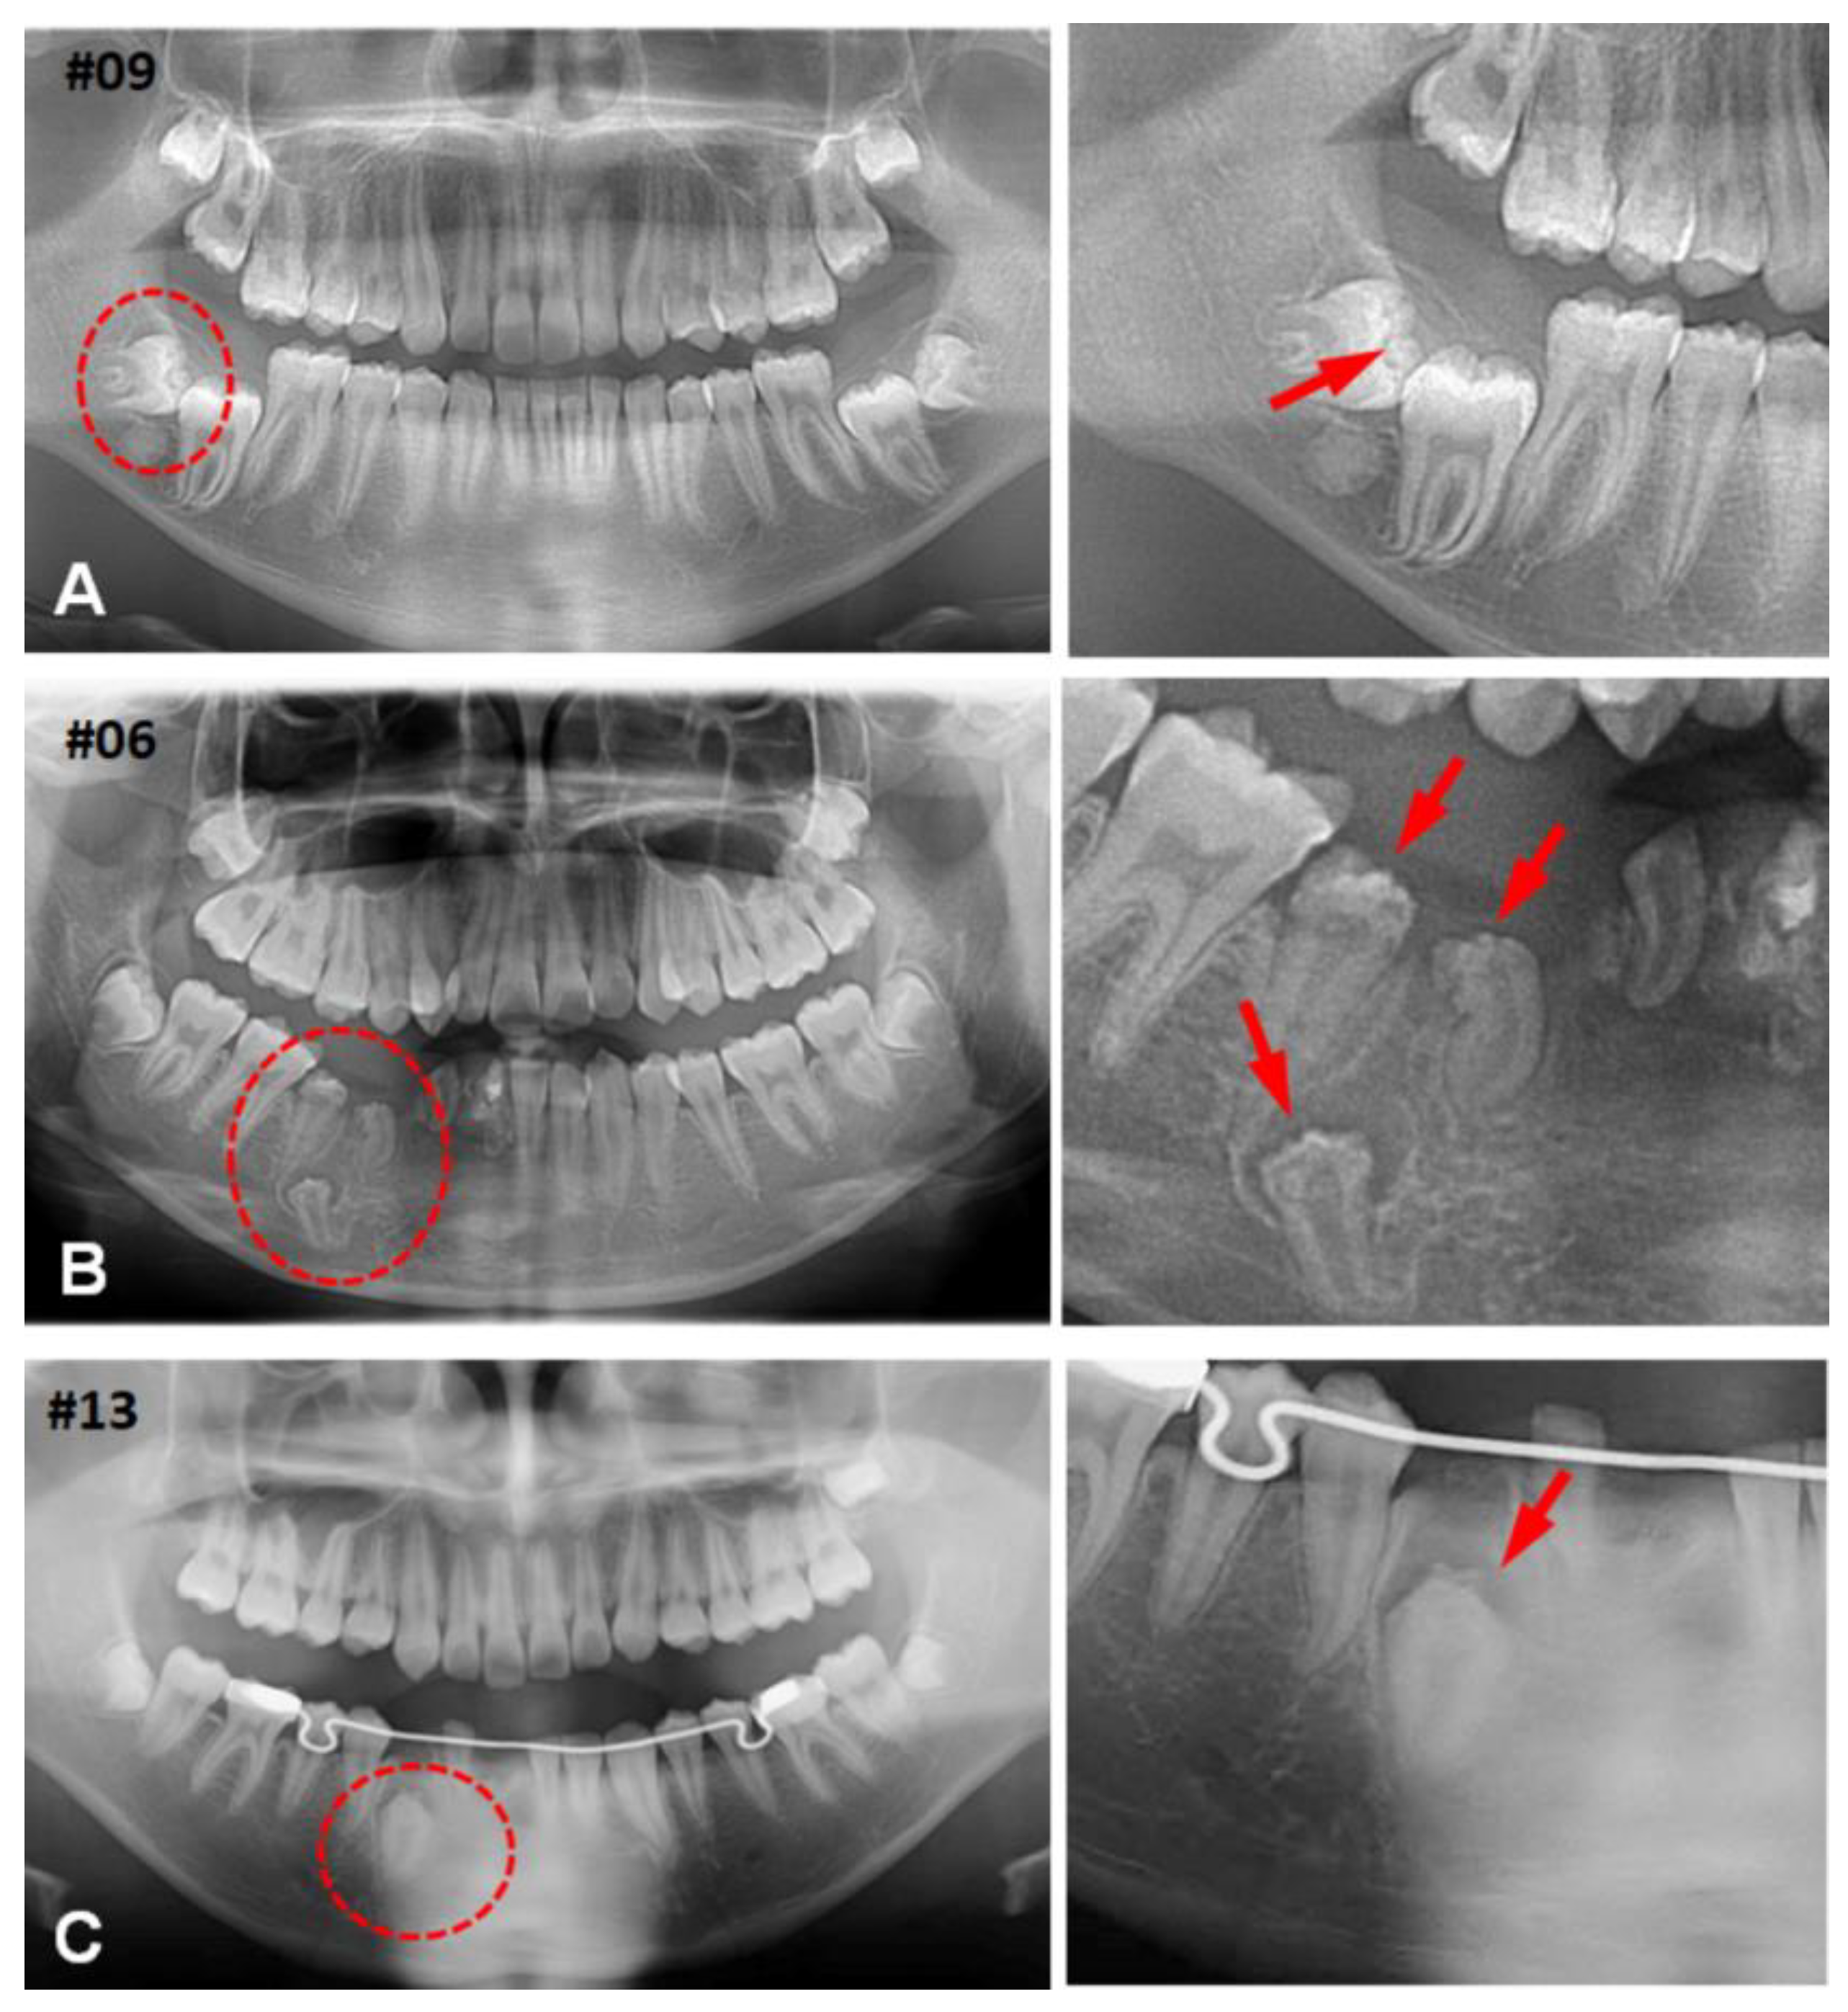

3.1. Clinical Characteristics of (CHDFs)

3.2. Histological Changes of HDFs